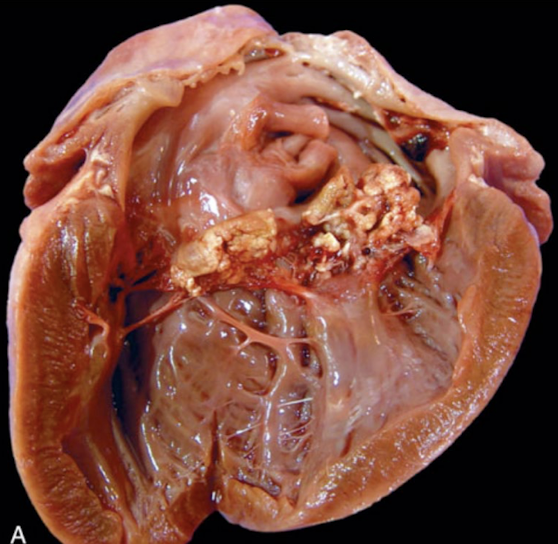

What is this showing?

valvular endocardiosis (myxomatous valvular degeneration)

a degenerative condition seen in middle aged to older male dogs that is a smooth raised off white to coalescing nodular thickening associated with the AV valve leaflets often associated with contraction of the valve leaflet

Which valve is commonly affected in valvular endocardiosis (myxomatous valvular degeneration)?

mitral valve » mitral +tricuspid valve

What dog breed is the poster child for valvular endocardiosis (myxomatous valvular degeneration)?

cavalier king charles spanie